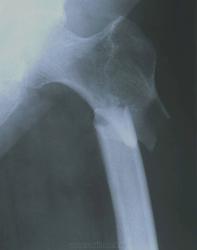

Но подвертельный перелом, все ж, не чрезвертельный, и в голове у простого рентгенолога должен быть маячок, что это ж-ж-ж неспроста. ///От 17% до 35% подвертельных переломов бедренной кости являются патологическими.///

В данном случае перелом безусловно патологический, его признаки минимальны, но совершенно верно указаны коллегами. Подтверждается это промежуточными снимками, к сожалению, качество их крайне низкое для демонстрации, но если получится что-то вытянуть, покажу.

Мда, метастаз

Подвертельный перелом изначально был патологическим.

Как мне кажется: участок остеолитической деструкции с нечеткими контурами в проксимальном отломке у края перелома, да и метафиз кажется поротичным.

Вы правы. Случай верифицирован - метастаз аденокарциномы

В данном случае травма была, механизм перелома известен - "споткнулась и упала". Но само по себе наличие травмы не может исключить патологический характер перелома. Также верно и обратное: у пожилых людей случаются переломы на фоне остеопороза и при минимальной, иногда неотчетливой травме (у меня была пациентка, у которой ребро сломалось при кашле). Хочу обратить внимание еще на одну, больше клиническую, сторону проблемы: зачастую при длительном болевом синдроме и неэффективности лечения, лишь патологический перелом является поводом сделать первое рентгеновское исследование...